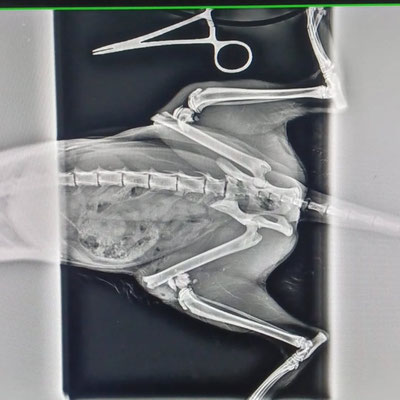

Die tierärztliche Untersuchung offenbarte das Ausmaß der Misshandlung: Eine Röntgenaufnahme zeigte eine Vielzahl von Nadeln im Magen, die der Hund – eingewickelt in einen Schwamm - offenbar mit dem Futter aufgenommen hatte.

In einer aufwändigen Notoperation, für die ein Spezialist hinzugezogen wurde, konnten 31 Nadeln erfolgreich entfernt werden. Die Kosten von 700 € bezahlte Pamela aus eigener Tasche, da der

Spezialist ausschließlich Barzahlung akzeptierte.